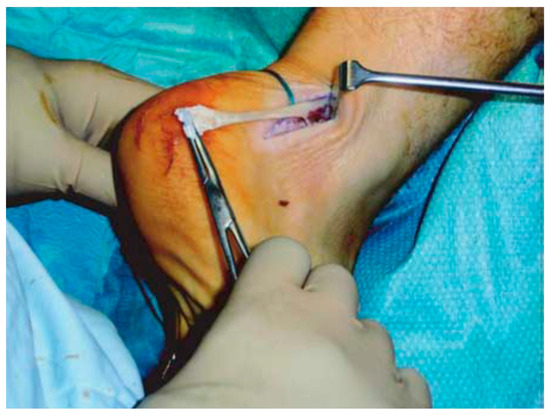

Good results have been reported for open surgery, with a success rate between 50% and 100% [121,122,123,124], removing the intra-tendinous lesions and more than 50% of tendon debrided (Figure 6).

Figure 6.

Open surgery for tendinopathy of the main body of the Achilles tendon. The tendinopathic tissue is identified and then excised.

Longitudinal incisions are made from tendon medial size avoiding sural nerve and short saphenous vein injuries [18]. Tendinopathic tissue is identified and removed, and it appear with a disorganised fibre bundles with a “crabmeat” appearance [18]. Any gap can be repaired using a side-to-side repair and can remain unsutured, or if significant loss tissue occurs, a tendon augmentation or transfer can be considered. Peroneus brevis (Figure 7) or flexor hallux longus (Figure 8) tendons are the most frequently used local tendon grafts [43,125,126].